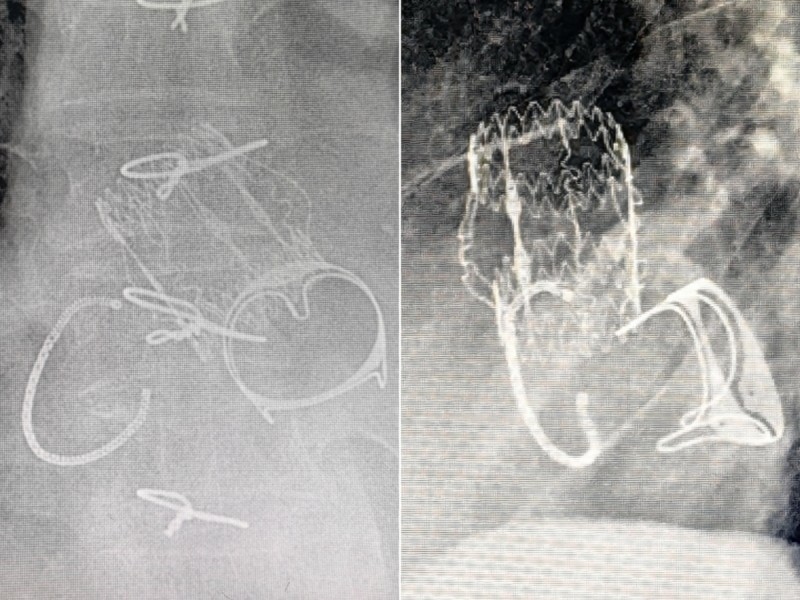

(图片3:免缝合瓣膜)

(图片5:术中免缝合瓣膜植入后)